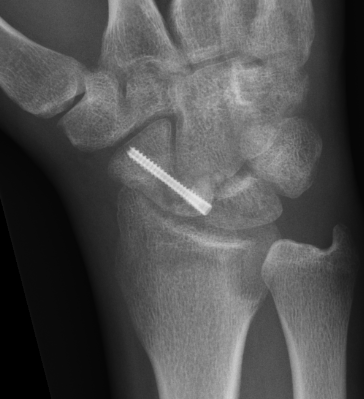

Post scaphoid ORIF

Xray

Proximal pole fracture with displacement and absorption

Waist nonunion

Technique

Volar approach

- clean fracture site of fibrous tissue with burrs if needed

- reduce deformity

- do not disrupt dorsal cortex

- place bone graft

- insert screws +/- plate